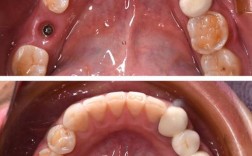

等了三个月,复查时拍CT看到骨结合得不错,医生安排第二次手术:安装愈合基台,其实比第一次手术简单,局麻后切开牙龈,露出种植体顶部,拧上愈合基台——它像个小帽子,能让牙龈围绕它长成自然的“牙颈形状”,手术半小时就结束了,术后反应比第一次轻,基本没肿,当天就能正常吃饭(只是不能吃太硬的)。

等牙龈长好(大概2周),医生给我取模,用一种蓝色的硅胶材料,往牙龈和基台周围一按,等凝固后取下来,就是牙齿的“模型”,医生说会送到加工厂做牙冠,让我等1-2周,取模时有点恶心,因为材料会流到喉咙,但医生动作很快,几秒钟就好。